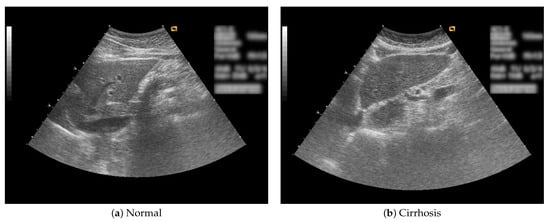

In this study, B-mode liver ultrasound imaging is focused on. B-mode ultrasound image data was provided by the collaborator. These data include 12 cirrhosis patients and 8 normal subjects. There were five ultrasound images per person. Figure 1 shows B-mode liver ultrasound images. Figure 1a,b show a normal and a cirrhosis liver, respectively. In this study, we focus on classifying regions of interest (ROIs) from the B-mode ultrasound images. Figure 2 shows examples of ROI images. The ROI images were manually cut out from the liver areas by a physician. A total of 200 normal and 300 cirrhosis ROI images were collected. Figure 2a,b show normal and cirrhosis livers. The size of each ROI image was 32 by 32 pixels. The grey level was 8 bits. Thus, the values ranged from 0 to 255. This is a typical two-class problem, normal or cirrhosis. From this figure, it seems difficult to visually classify a liver as normal or cirrhosis if one is not a physician because of noisy ultrasound images.

Figure 1. Liver ultrasound images.